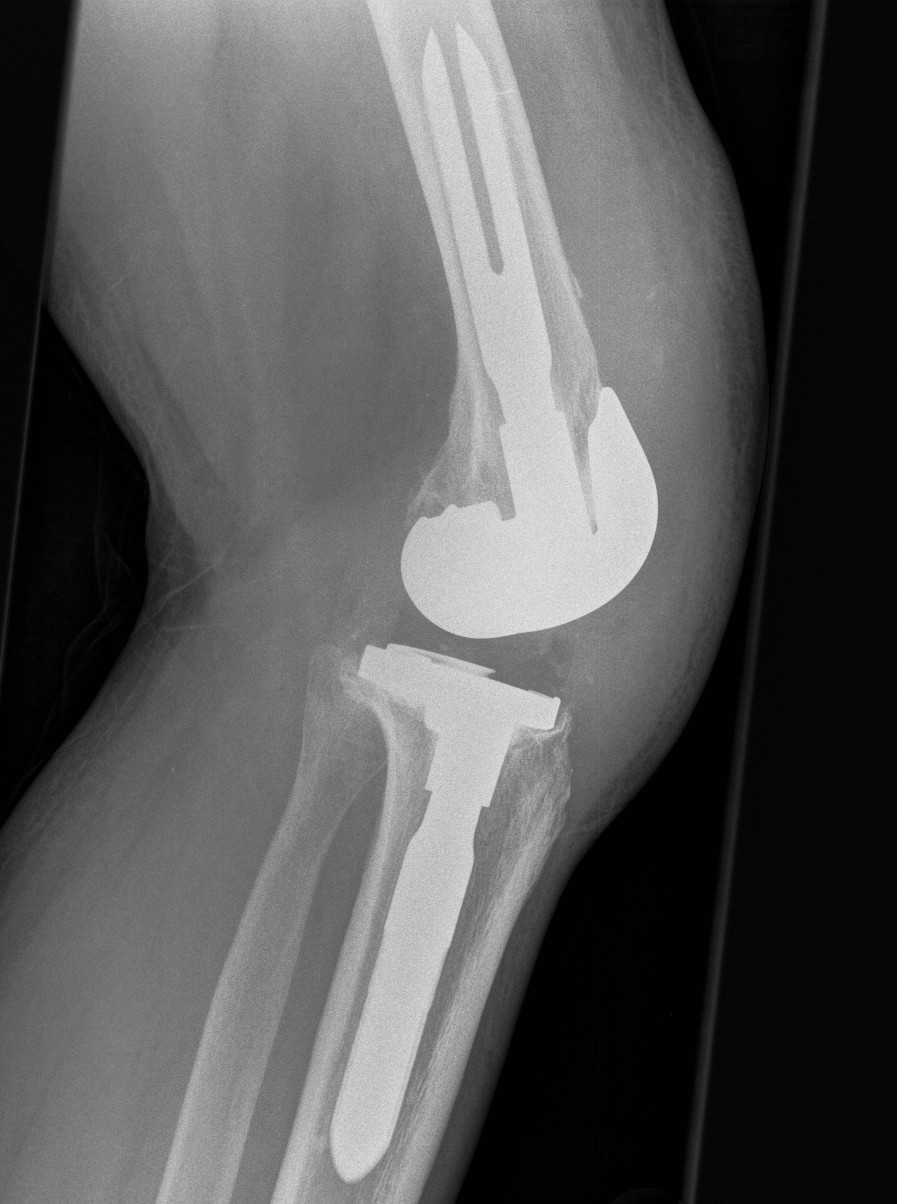

3. Tibial tuberosity osteotomy

- 6-10 cm long, 2 cm wide, 1 cm thick

- lateral periosteum intact / lever open laterally

- bypass osteotomy with stem

- need to wire back around the tibial stem

- place wires before definitive stem

- drill holes medially and laterally

- can use diverging screws as well